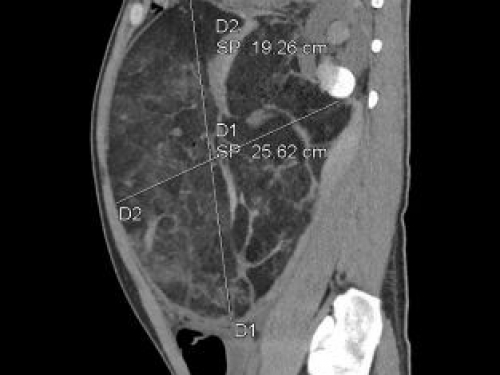

【媒体贵医】10.4公斤篮球大小肿瘤破裂,贵医附院多学科协作成功切除

【媒体贵医】22厘米腹膜后巨瘤“炸弹”成功“拆除”